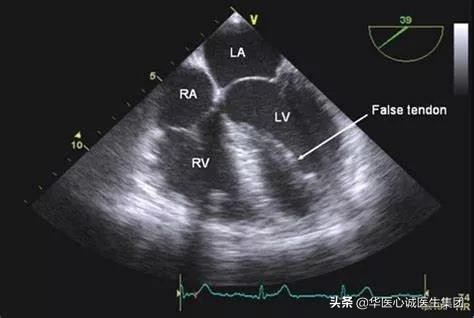

六、左心室假腱索

可起源于左心室任何一侧壁,多见于前壁和乳头肌,终止于室间隔膜部、肌部或心尖部。少数假腱索起止于乳头肌、心尖部和游离壁之间,极少数位于左心室流出道和主动脉瓣。

- 临床意义:含有一些传导束,可能引起早搏。

- 超声表现:

粗大的假腱索

从心尖处延伸到室间隔膜部。

细小的假腱索

游离壁和室间隔之间进行连接,且合并室壁瘤。

右图显示的是短轴切面。

有些学者认为左心室假腱索含有传导细胞或者异位起搏细胞。少数患者在心脏舒张时,假腱索受到牵拉,可能会导致室性早搏。但多数患者没有任何症状。